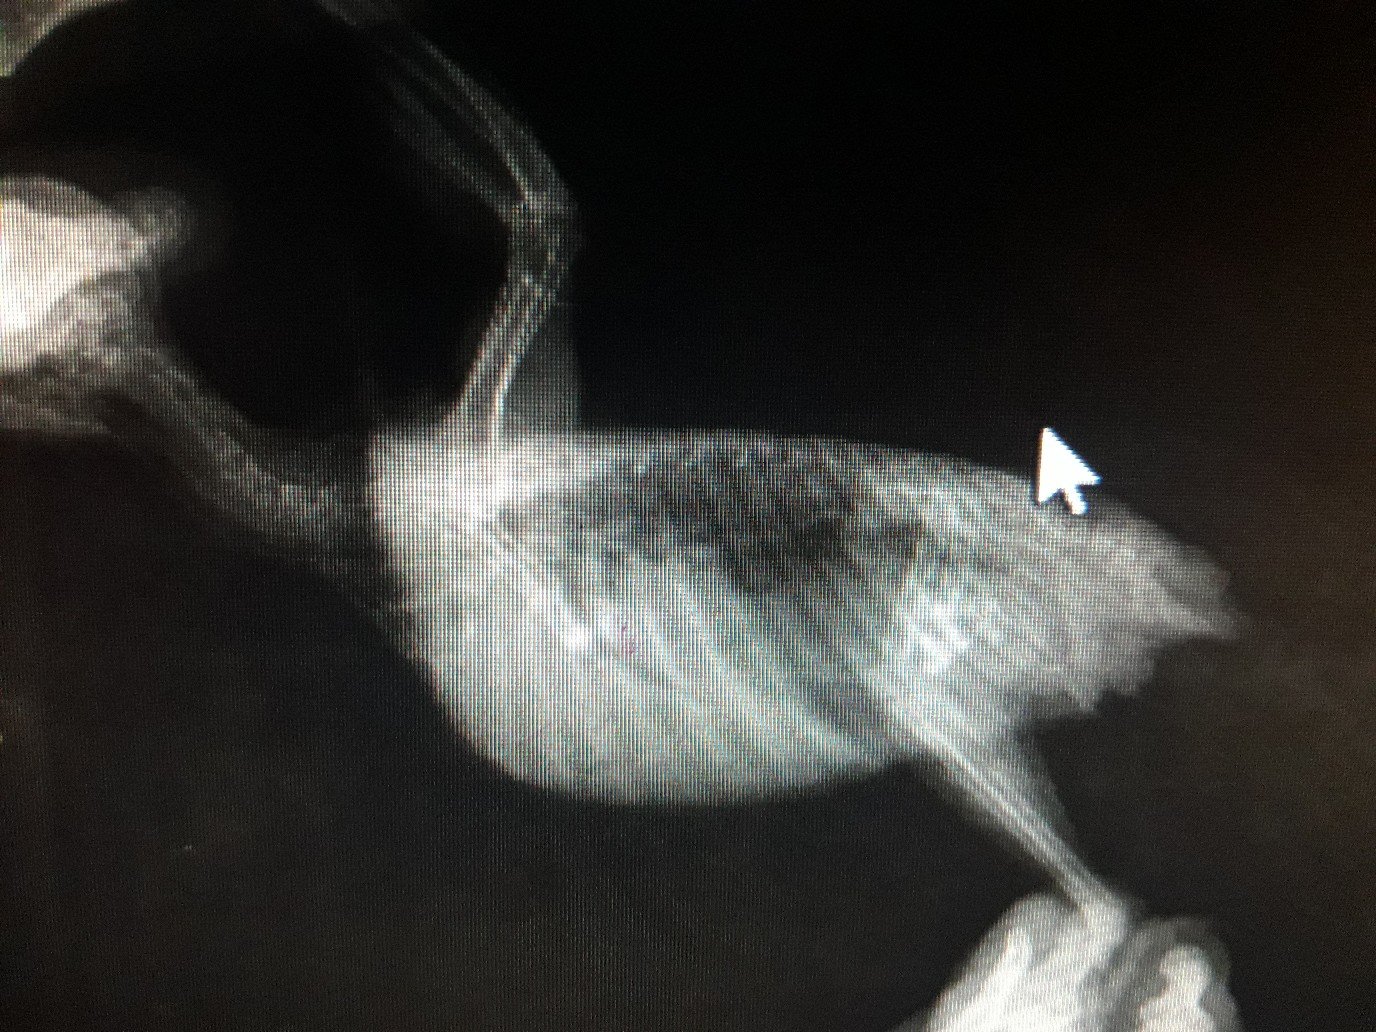

Малыш 87 Опубликовано 12 декабря, 2019 Автор #23 Опубликовано 12 декабря, 2019 Делали ренген Сказали вроде как немного увеличена

Малыш 87 Опубликовано 13 декабря, 2019 Автор #28 Опубликовано 13 декабря, 2019 Мне отдали только диск с ренгеном

Кузяныч Опубликовано 13 декабря, 2019 #31 Опубликовано 13 декабря, 2019 @Малыш 87, а результаты анализа помёта на листе бумаги вам выдавали на руки? Все эти расспросы я затеял потому что при увеличении печени (гепатомегалии) больше подходит гепатовет. Гептрал, как по мне, назначают при явных тяжёлых поражениях, одним из симптомов которых является помёт жёлтого / оранжевого цвета. И ещё я хотел бы увидеть результат анализа помёта чтобы сопоставить их с внешним видом помёта на предоставленном вами снимке.